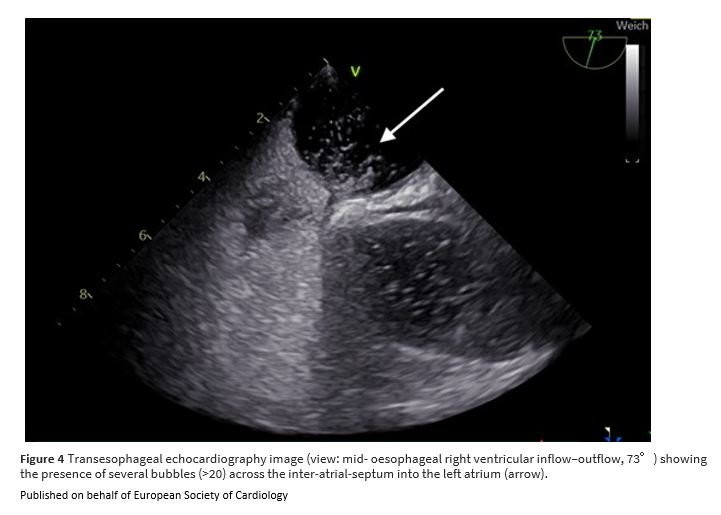

Unexpected paradoxical embolisation following catheter-directed thrombectomy with the FlowTriever™ system in a case of pulmonary embolism bit.ly/41n1RlZ

#EHJCaseReports #EchoFirst @aayshacader @KardiologieHH @ANazmiCalik @EHJCREiC @TJ_Yeo @Phiso_de @FarhanaAra